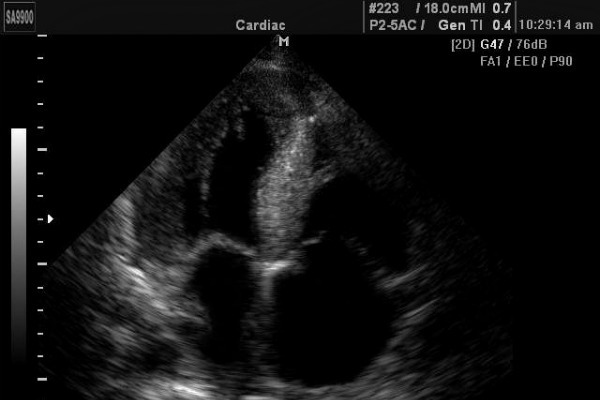

Двухмерная или В-эхокардиография в отличие от предыдущего варианта позволяет получить динамическую черно-белую картинку, которая движется согласно сокращениям органа. Во время сеанса врач фиксирует данные о размерах желудочков, предсердий, толщине миокарда, работе клапанов и прочие характеристики.

- Двухмерный метод. На экране можно увидеть привычную картинку кт и маленький экранчик с результатами работы сердца. Можно увидеть его сокращения и наполнение сосудов кровью. Измеряется сократимость желудочков и степень подвижности клапанов сердца. Таким способом обнаруживается аневризма аорты, опухолевидные образования и тромбозы.